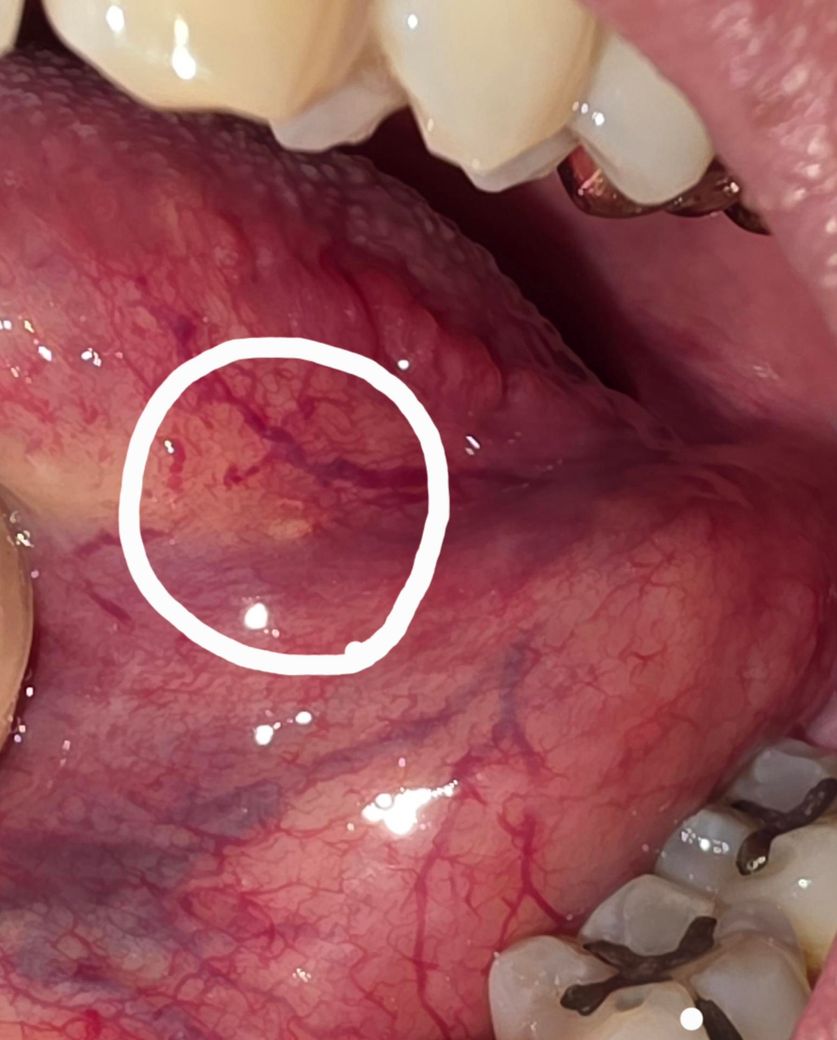

혀 엽상돌기 밑에 노란 돌기 같은 것이 생겼습니다.

엽상돌기 밑 부분에 노란색 돌기를 발견했습니다.

볼록 튀어나온 느낌보다는 정말 미세하게 표면이 올라와 있습니다.

사진 상 흰색 원 안의 부분입니다.

• 1번 째 사진